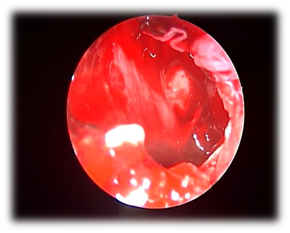

Figure 2 endoscopic sphenoidotomy for bacterial sphenoid sinusitis./p>

Figure 4 Mud and mucin in isolated sphenoid allergic fungal sinusitis.